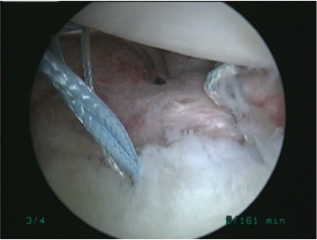

手術所見

| 前方関節唇損傷 | 損傷部位を縫合中 | 縫合終了 |

![]()  |